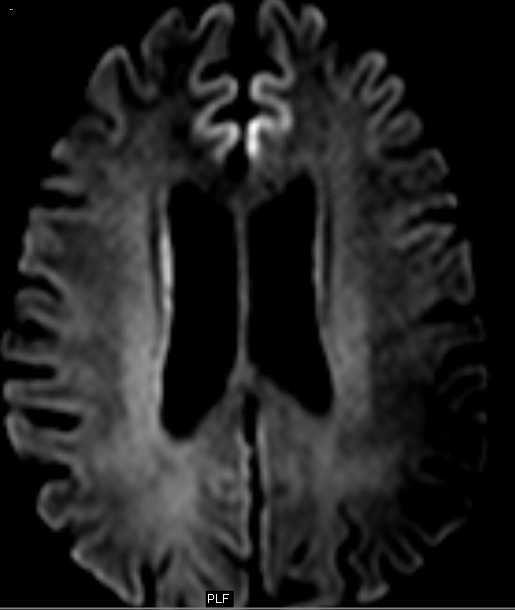

From www.cureus.com

Cureus Imaging Manifestations of CreutzfeldtJakob Disease and Case Series Crutch Jacobs Disease Once symptoms start, the condition worsens quickly, causing a. It affects the brain and causes dementia and other. A brain biopsy or an exam of brain tissue after death, known as an autopsy, is the gold standard to confirm the presence of creutzfeldt. Also called classic cjd, it worsens quickly. Crutch Jacobs Disease.